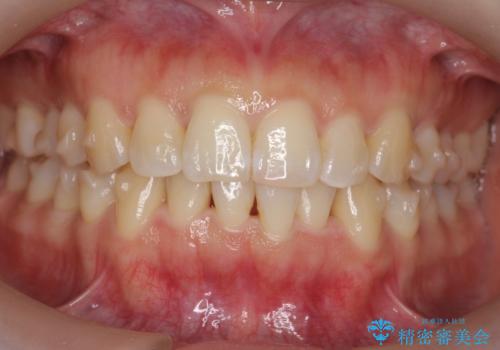

下の前歯のがたつき インビザラインで

- 前歯のがたつきを主訴に来院。

インビザラインで上下の前歯をわずかに削って並べました。

下の歯の叢生を並べると多少ブラックトライアングルがでることがあります。